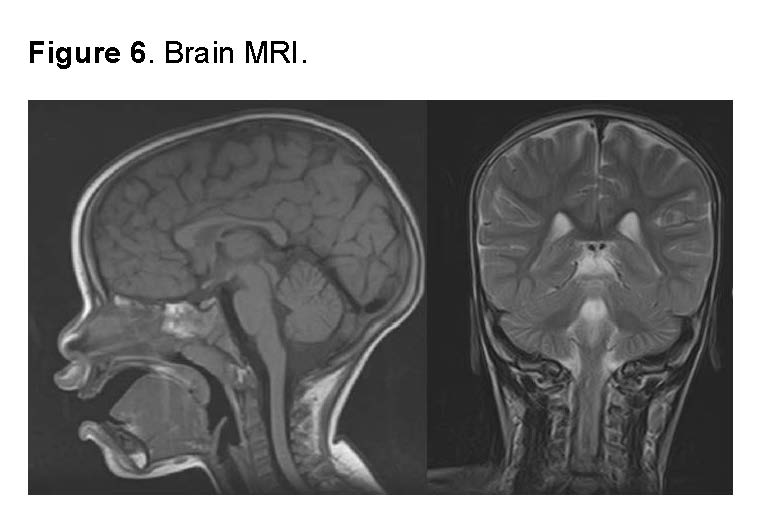

Brain MRI: The brain MRI showed no evidence of structural abnormalities, lesions, masses, signs of infection or inflammation, or vascular abnormalities. The morphology and signal of intracranial structures were normal, including white and gray matter, ventricles, and subarachnoid spaces. No signs of cerebral edema or midline shift were observed. The study is consistent with a neurological exam without pathological findings.